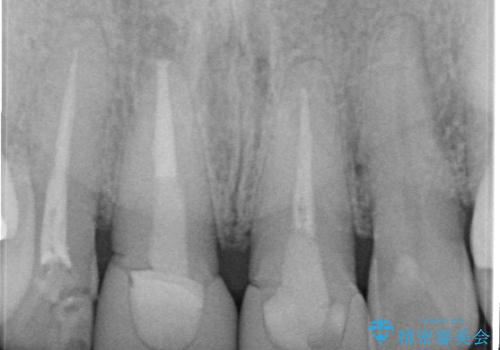

根管治療について

保険根管治療は回数がかかることが多く、終了予定がわかりにくいです。

当院では、根管治療は長い時間のご予約を頂き、多くの場合2~3回で終わります。

根管治療は歯内の治療なので患者様には見えない場所ですが、ここが細菌で汚染されると激しい痛みや長引く違和感の原因になります。

当院では、清潔な治療を徹底し、顕微鏡を使用した精密な治療を行っています。

症状や根管の状態により、治療金額が異なります(5~10万円目安)。治療回数による費用負担の増減はありません。

根管治療専門医をご紹介させて頂く場合がございます。